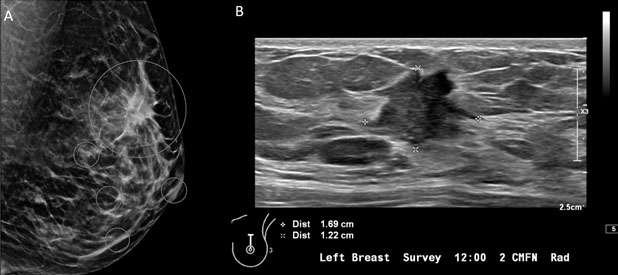

1. Oval: an oval mass (Figure 1) is elliptical or egg-shaped (may include two or three undulations).

Mammography: Masses Figure 1

Figure 1: Targeted ultrasound examination of the right breast demonstrated an oval mass with circumscribed margins measuring 7 x 4 x 7 mm seen at 3 o'clock located 2 centimeters from the nipple. Oval mass is probably benign, sonographic follow-up in 6 months is recommended. BI-RADS Category 3: Probably Benign Finding.